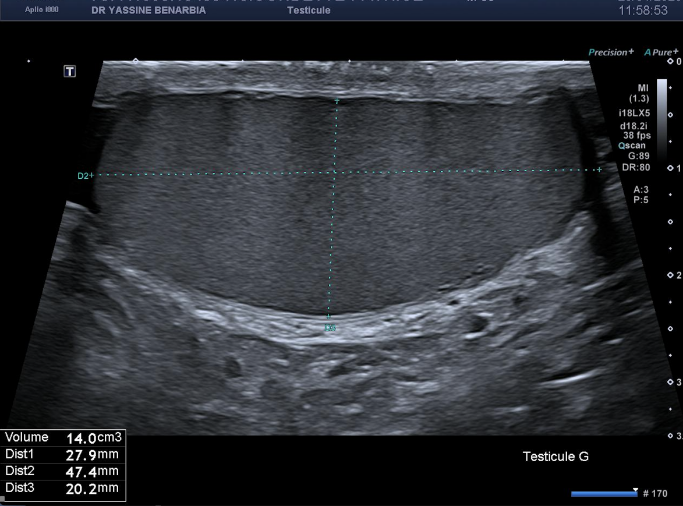

L'échographie retrouve des testicules de morphologie, taille et vascularisation strictement normales bilatéralement. Les épididymes sont également normaux, sans signe d'inflammation. Le Doppler couleur montre une vascularisation testiculaire symétrique et physiologique.